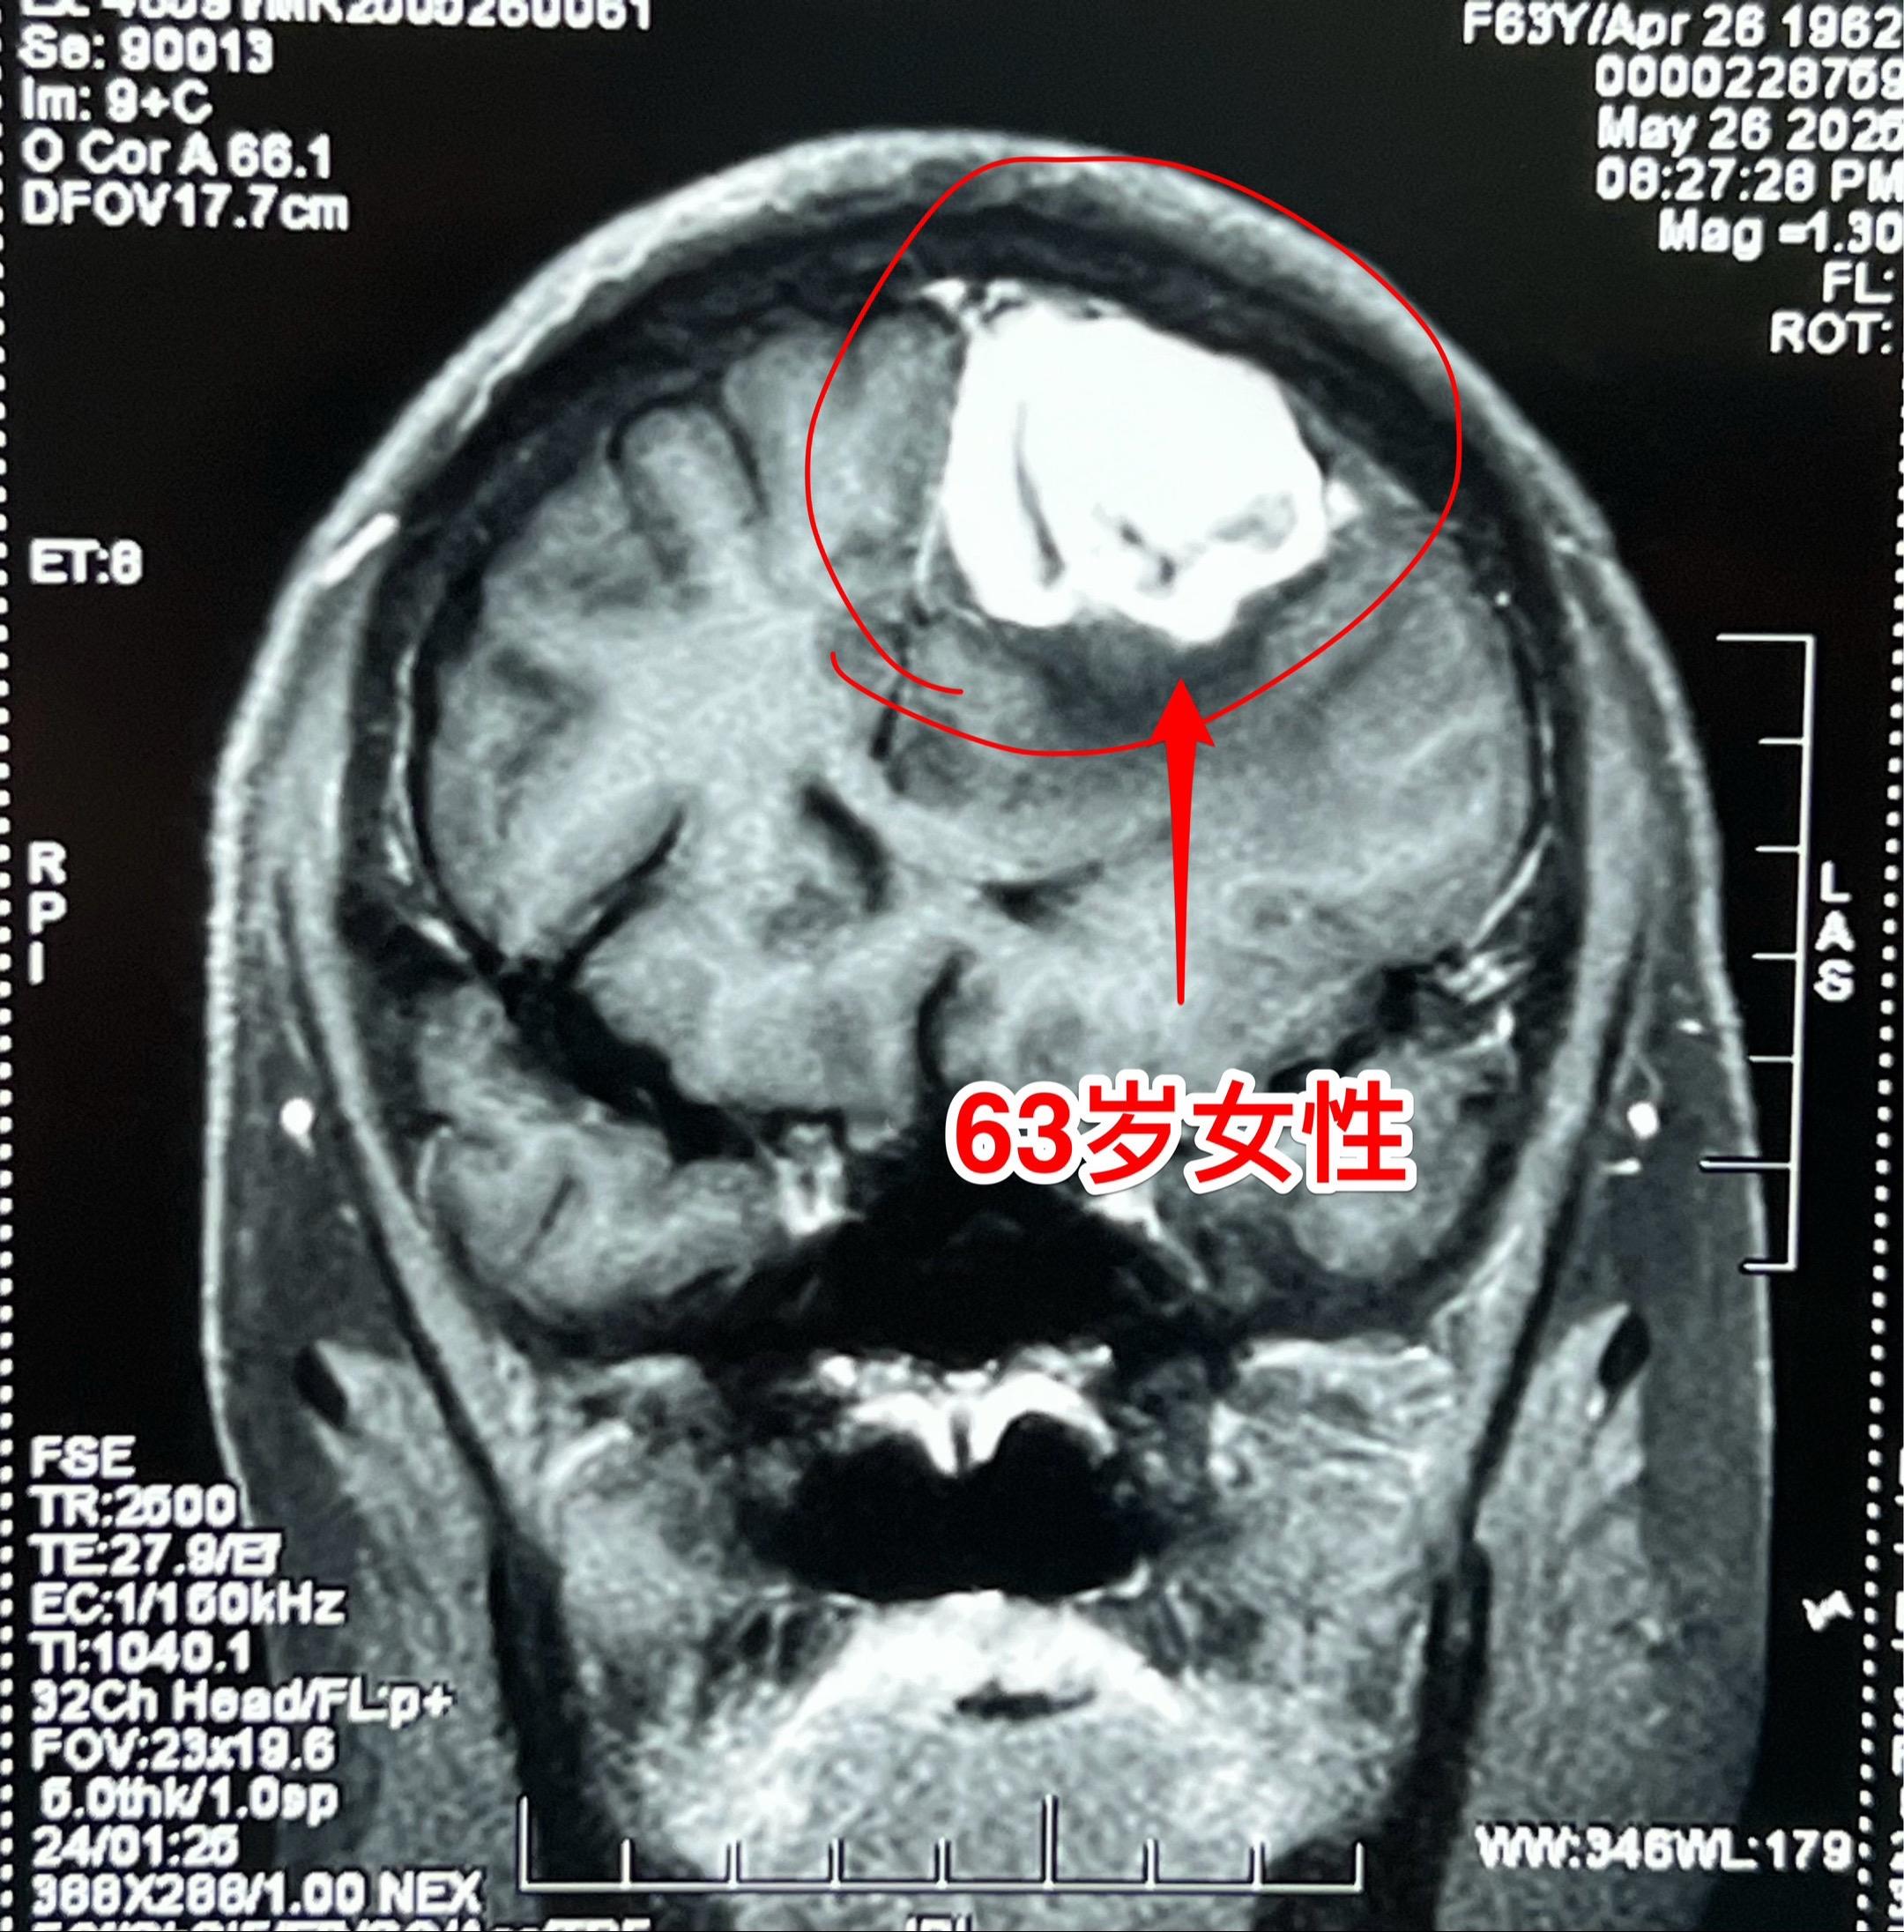

脑部原发的淋巴瘤和血液科的淋巴瘤不一样。63岁的因头痛、右腿活动无力经过检查发现了脑部肿瘤,见图。 通过开颅手术切除了肿瘤,手术后右腿无力症状改善了。病理报告是:淋巴瘤(大B细胞淋巴瘤)。 脑部原发的淋巴瘤和血液科的淋巴瘤很不一样。脑部原发的淋巴瘤发病率呈上升趋势,原因不明。在艾滋病病人中其发病率是免疫功能正常者的1000倍。 脑部原发淋巴瘤对化疗和放疗都敏感,通过适当的治疗,预后还是不错的。淋巴瘤